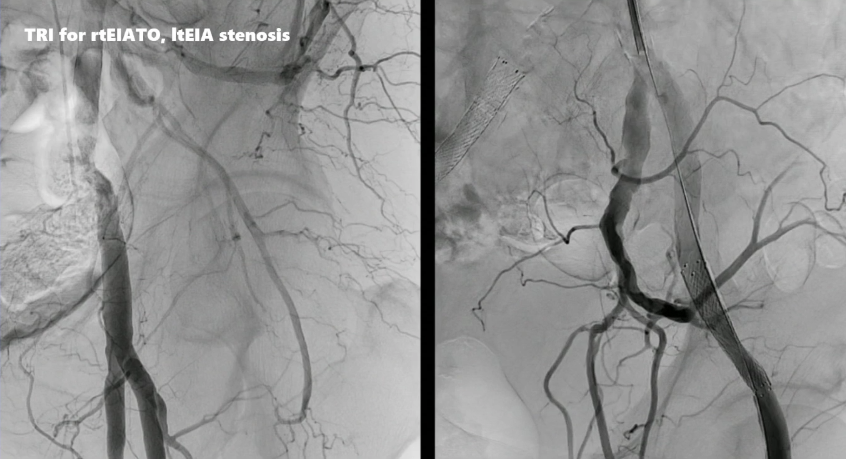

病例二:左侧髂外动脉完全闭塞

术者采用IVUS引导下精准导丝通过。目前,支架已有适用于经桡动脉介入的长鞘版本,因此可经桡动脉置入覆膜支架,通过造影和IVUS进行评估,可见支架植入后即刻效果理想。